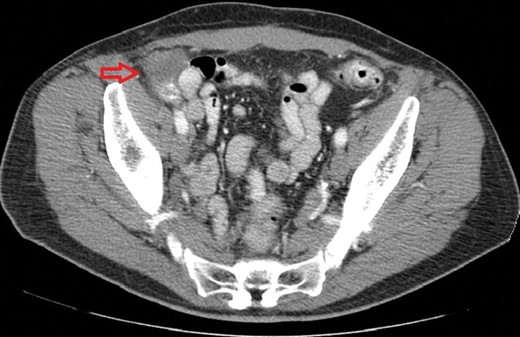

A 72-year-old man was referred for resection of a cecal mass that was found on routine colonoscopy (Fig. 1). The patient denied history of blood per rectum, change in bowel habits, abdominal pain, nausea or weight loss. The patient had a significant past medical history for prostate cancer for which he underwent prostatectomy and chemo-radiation therapy. He also underwent open repair of bilateral inguinal hernias in the remote past; the operative notes were not available to us. Tumor markers (CEA and CA19-9) and routine blood tests were unremarkable.

Colonoscopy: view of the cecum; a broad-based mass is present in the right lower corner of the photo. The mucosa appears normal and did not exhibit erythema or ulcerations.

The mass was found in the cecum during routine colonoscopy (Fig. 1); it had raised borders, did not have a stalk and was not associated with mucosal erythema or ulceration. Biopsies showed normal colonic mucosa. A computed tomography (CT) scan of the abdomen showed a 3.3 × 4 cm mass that compressed the wall of the cecum. There was no associated lymphandenopathy or liver lesions (Fig. 2). Based on these findings, we could not conclude if the aforementioned mass was intramural or extramural to the cecum. Due to the uncertainty about the location of this mass (intramural versus extramural) and the inability to rule out a neoplasm, we proceeded with a diagnostic laparoscopy with the possibility of resection of the cecum. Intraoperatively, we found that the right inguinal hernia had been repaired using a plug-and-patch technique. The mesh plug was fixed in the preperitoneal space and had not violated the peritoneal layer. The ‘Plug’ had not fully deployed in the preperitoneal space and had retained a cone-like shape. The wall of the cecum appeared normal and there were no masses in its anterior wall. An intraoperative colonoscopy was done to confirm the absence of a mass; upon insufflation of the colon, it became apparent that the cecal wall was pressed against the non-deployed plug thereby creating the impression of a mass with extrinsic compression.